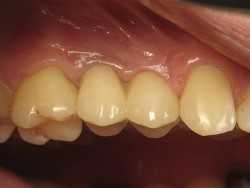

Тотальное протезирование верхней челюсти металлокерамическими коронками с опорой на имплантаты Astra-Tech (Швеция) с левой стороны, и на свои зубы с правой стороны